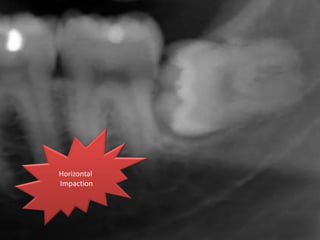

Angulation of impaction

Based on Winter's classification, the angle between the

longitudinal axis of the second and third molars

Mesioangular

impaction

Horizontal impaction

Vertical

Distoangular